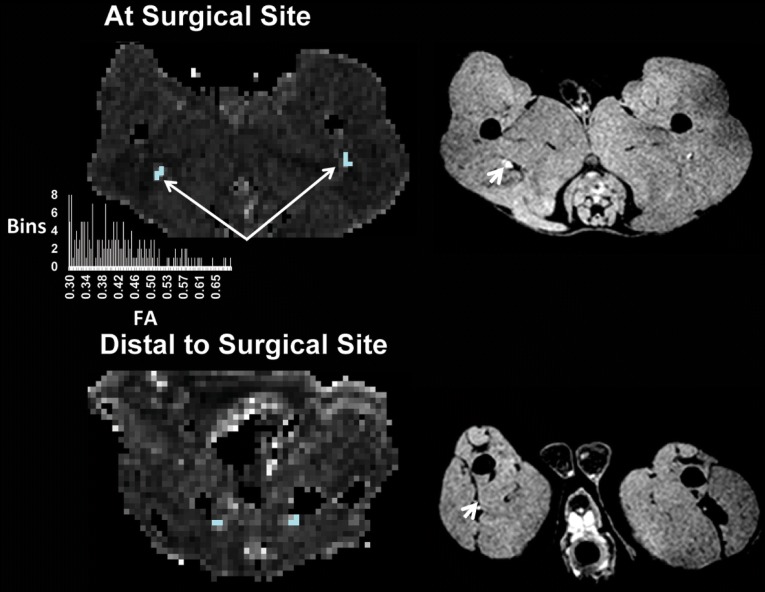

Fig. 3.

Segmentation of the sciatic nerve. Tensor fitting was performed with DTI Studio (www.mristudio.org) to obtain DTI maps after motion and distortion correction by linearly registering all gradient directions to the b = 0 map. Sciatic nerves were manually segmented using the fractional anisotropy (FA) map (left panel) as a mask by thresholding the nerve (minimum, maximum FA = 0.3, 0.8) and using the reversed fast imaging with steady state free precession sequence for anatomical nerve localization (right panel). A region-growing algorithm, using a custom code written in Interactive Data Language (www.harrisgeospatial.com), was employed to segment the entire nerve length. DTI measurements were extracted from voxels between the 25th and the 75th percentiles of the FA histogram to mitigate partial volume effects at the peripheral margins of the nerve. The surgical site was located proximal to the midpoint between a line drawn between the greater trochanter and ischial tuberosity (right panel, white arrows). Similarly, the distal site was located 3 mm distal to the surgical site on the FA map. Only the voxels inside the mask were included in the analysis